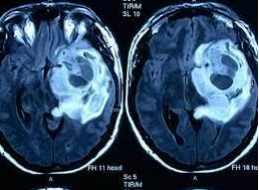

En octubre de 1971, se da la primera exploración de un paciente mediante el uso de la TC, en el Hospital Atkinson Morley, Hounsfield y Ambrose observaron las primeras imágenes del paciente, mostraba un tumor quístico circular en el lóbulo frontal. El cirujano que le realizó la operación al paciente informó que el tumor se encontraba exactamente en el lugar en el que aparecía en la imagen.